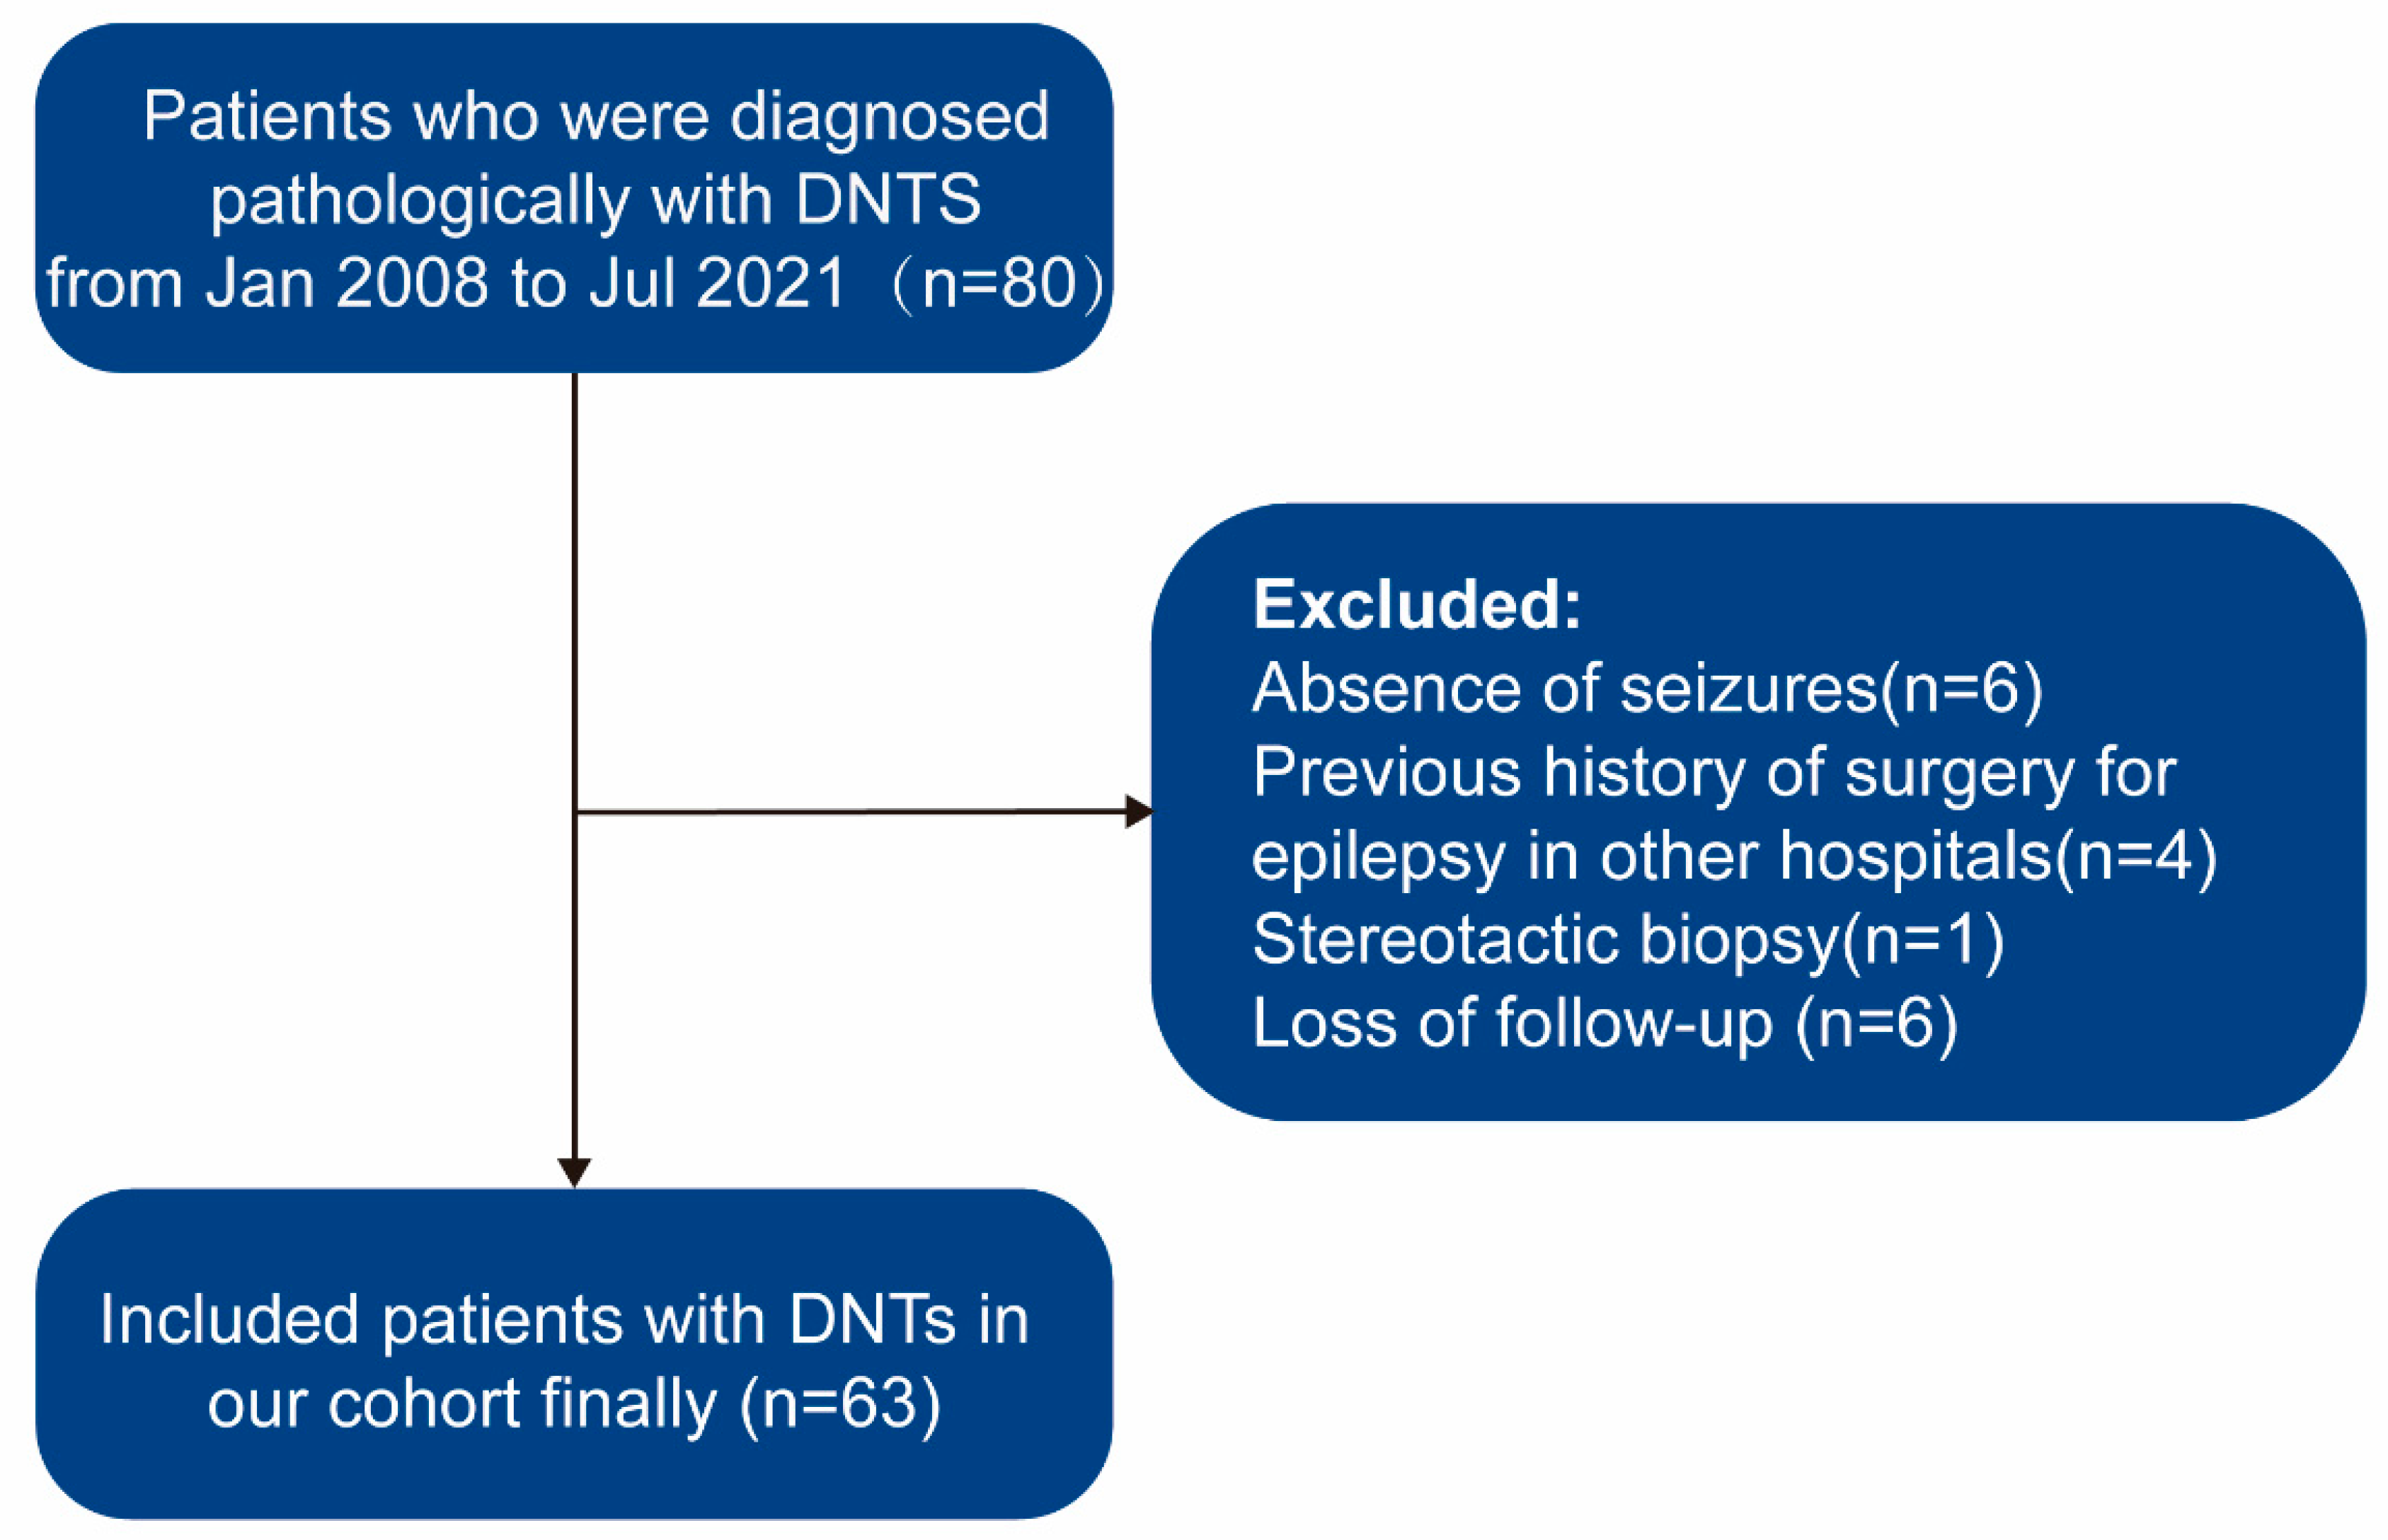

2.1. Patient Selection